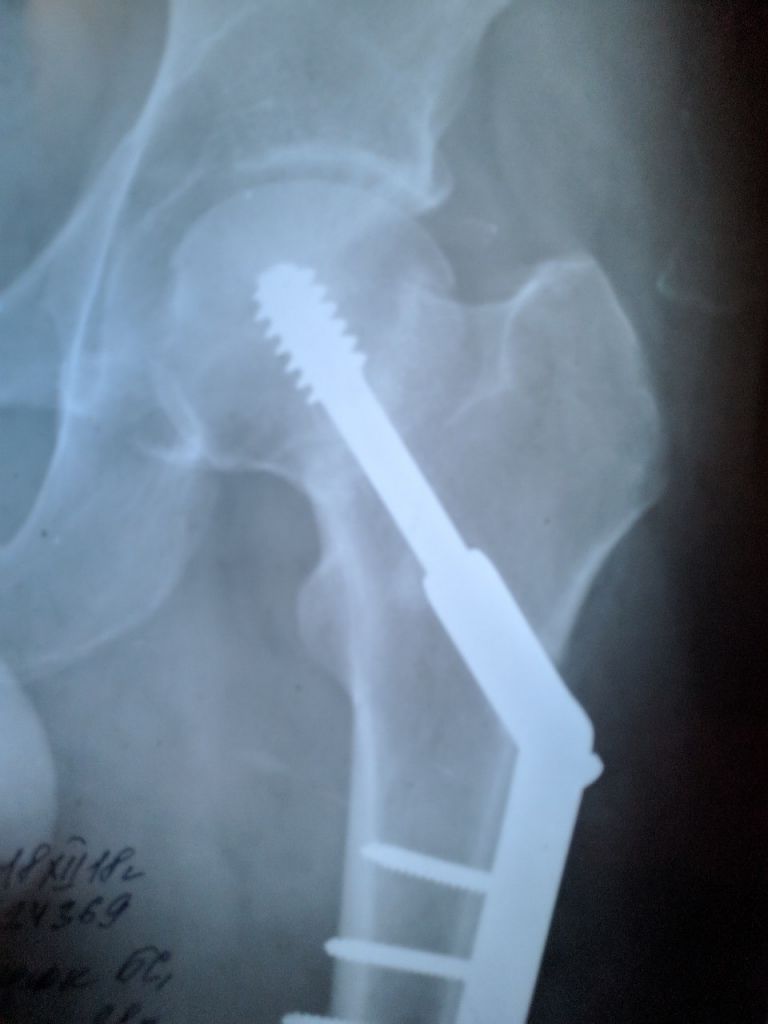

Добрый вечер всем img/bq  img/kefir

Спешу поделиться радостной новостью в канун нового года  img/aw

Spoiler

PUB

К весне, согласно графика реабилитации, сменю трость на велосипед img/be  img/ba

Фруктовый гусЬ, перелом шейки бедра.... у меня так было давно....

хромал долго.... в школе меня "хромой" дразнили..